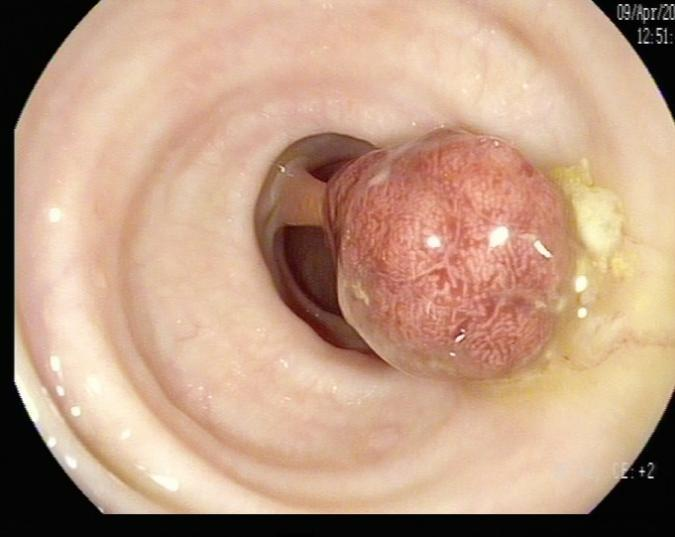

(3)邓先生(54岁,乙状结肠息肉,图3)

图3

病理诊断:(乙状结肠)管状腺瘤。

解读:这是最常见的腺瘤类型。若未发现高级别瘤变或癌变,属于相对早期的癌前病变。但放任不管,其癌变风险随时间推移而增加。距离癌:潜在风险,癌前病变早期。